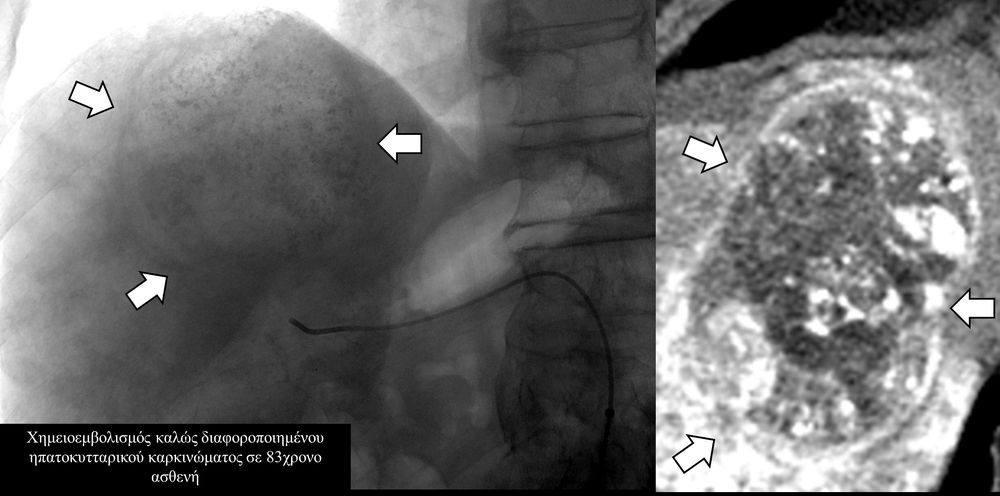

Ο χημειοεμβολισμός είναι μέθοδος τοπικής χημειοθεραπείας για πρωτοπαθή και δευτεροπαθή νεοπλάσματα του ήπατος. Σκοπός του είναι η τοπική έγχυση χημειοθεραπευτικού σε κλάδους της ηπατικής αρτηρίας, ώστε να επιτευχθούν υψηλές συγκεντρώσεις τοπικά στην ηπατική εξεργασία χωρίς να προκαλούνται οι συστηματικές επιπλοκές τοξικότητας του χημειοθεραπευτικού. Επιπλέον προκαλείται τοπική ισχαιμία στην περιοχή του όγκου από τα εμβολικά υλικά-μικροσφαιρίδια εμβολισμού.

Ο χημειοεμβολισμός έχει καθιερωθεί σαν θεραπεία εκλογής στο ενδιάμεσο στάδιο του ηπατοκυτταρικού καρκινώματος.